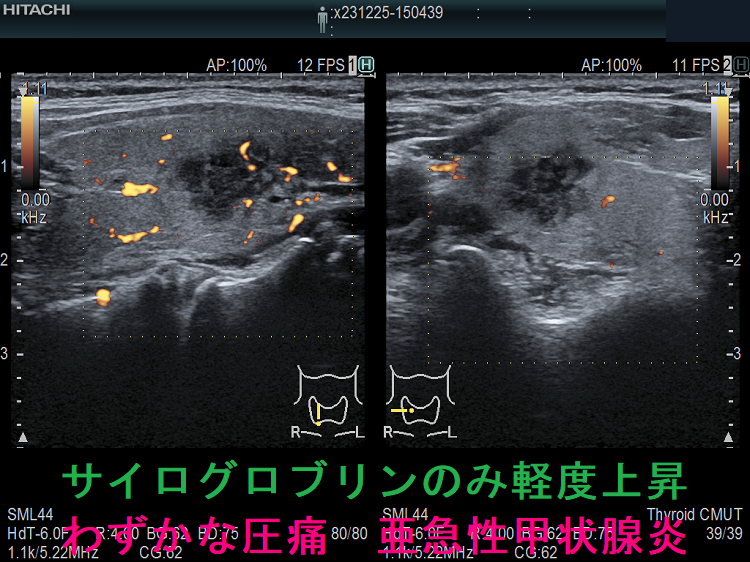

また、下の画像は、甲状腺機能正常橋本病患者において、特に自覚症状ないものの、数年来正常だったサイログロブリンのみが軽度上昇。原因を調べるため行った甲状腺超音波(エコー)検査で、亜急性甲状腺炎が見つかりました。低エコー部を圧迫すると、患者自身も気が付かなかった軽度の圧痛あり。

発熱、頸部腫脹と疼痛・圧痛、圧痛部に一致した低エコー域、炎症反応を認め、典型的な亜急性甲状腺炎だが、甲状腺機能正常で甲状腺中毒症は無く、サイログロブリンだけ上昇するケースもあります。

- 67歳女性、WBC 6300/μL、CRP 2.4 mg/dL と軽度高値。FT4 1.09 ng/dL、FT3 3.23 pg/mL、TSH 1.34 μIU/mL、TgAb・TPOAb陰性、血中サイログロブリン 290.0 ng/mL と高値

- 75歳女性、WBC 7500/μL、CRP 4.0 mg/dL と中等度高値。FT4 0.97 ng/dL、FT3 2.38 pg/mL、TSH 2.07 μIU/mL、TgAb・TPOAb陰性、血中サイログロブリン 244.4 ng/mL と高値